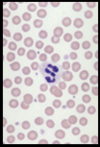

Name this WBC

Neutrophil